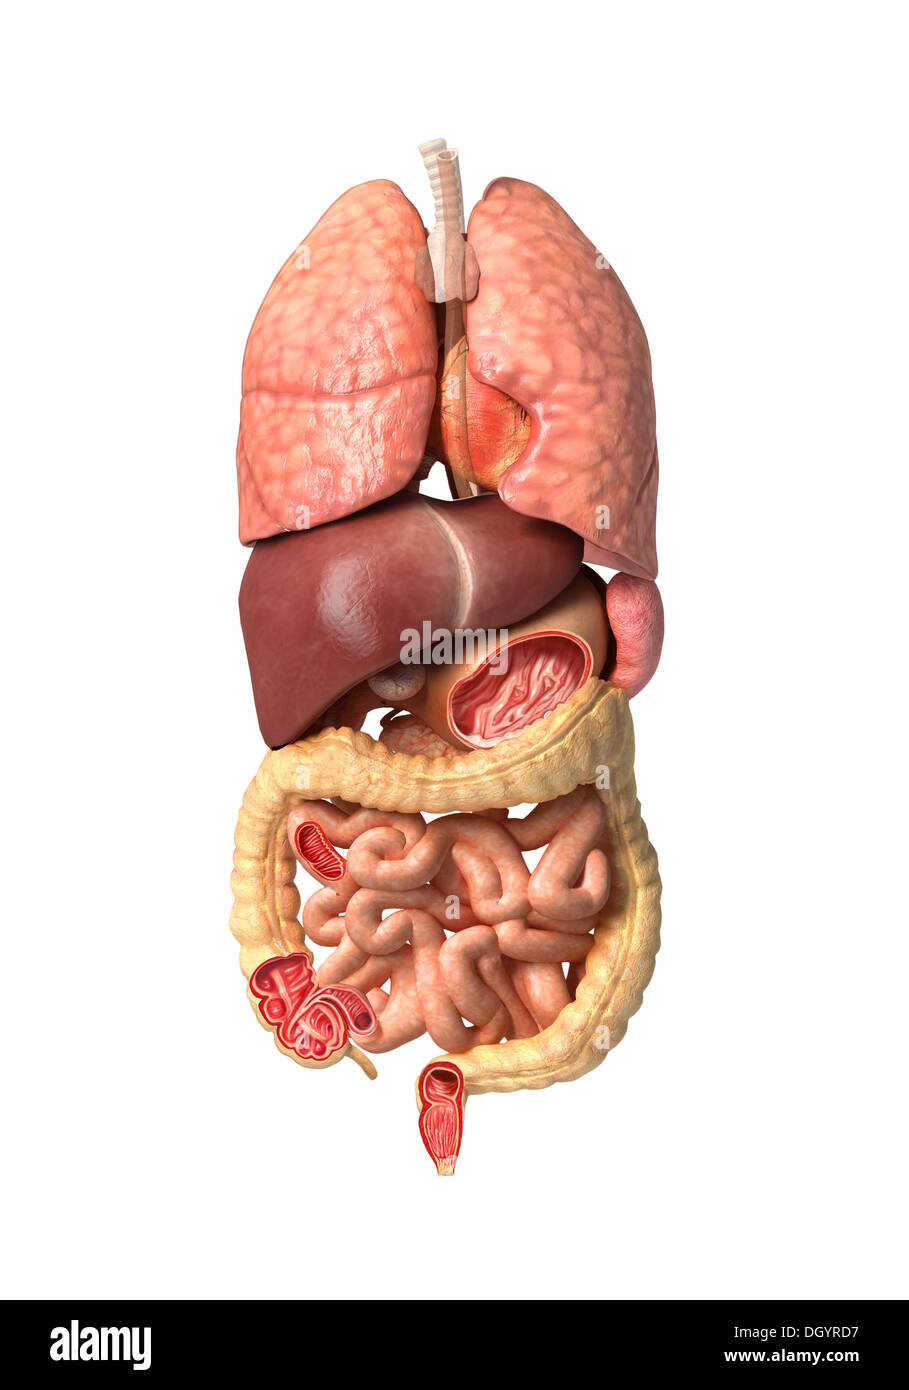

RFDGYRD7–Männliche Anatomie, inneren Organe allein, volle Atmungs- und Verdauungssystem, mit einigen Organen Cutaway. Anatomie-Bild.